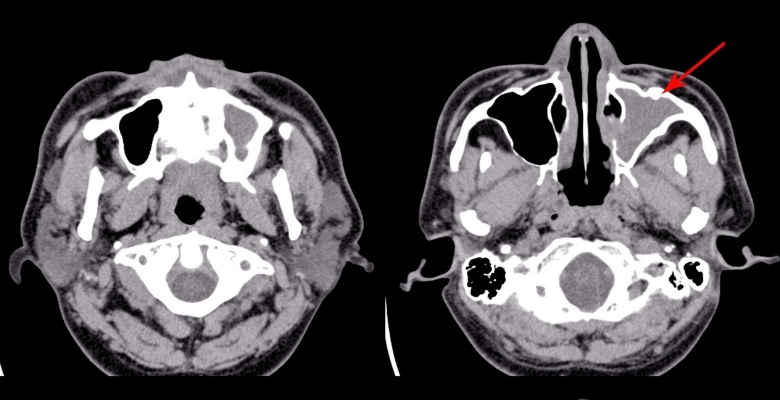

Obstrução nasal pediátrica: investigadores otimizam teste rápido que simplifica a triagem

Investigadores europeus anunciaram a validação de um teste rápido e simples, o oral screen test, que facilita a triagem de obstrução nasal em crianças entre os 4 e os 15 anos de idade. Nesta nova abordagem, as crianças utilizam um dispositivo oral em silicone que, segundo os autores, causa desconforto…